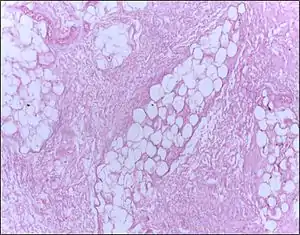

| Micrograph of breast tissue showing fat necrosis. H&E stain | |

Fat necrosis is a form of necrosis that is caused by the action of lipases on adipocytes.[1][2]

In fat necrosis, the enzyme lipase releases fatty acids from triglycerides. The fatty acids then complex with calcium to form soaps. These soaps appear as white chalky deposits.[3]

Fat necrosis is the pattern of damage associated with the destruction of adipose tissue by trauma, hypoxia, or lipase digestion (e.g. pancreatitis). In the classic case of fat necrosis in severe acute pancreatitis, the necrosis arises because adipocytes in the peritoneum are broken and digested by inappropriately activated pancreatic enzymes. Stored triglycerides in the adipocytes are released and split by pancreatic lipases into fatty acids and glycerol molecules. The resultant fatty acids react with extracellular calcium to make calcium soaps (i.e. fatty acid salts) that give fat necrosis its characteristic chalky-white appearance. Fat necrosis is an example of dystrophic calcification because the calcification occurs at normal serum calcium levels.[11]